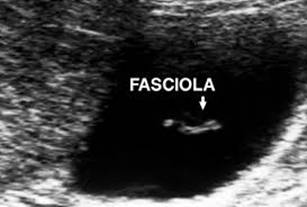

Chẩn đoán huyết thanh học có giá trị vì độ nhạy, đặc hiệu cao cả giai đoạn mạn tính và cấp tính. Đôi khi, sự di chuyển của sán trong túi mật hoặc đường mật được phát hiện qua siêu âm và được xem như là một công cụ chẩn đoán tốt bệnh SLGL và có độ nhạy hơn cả CT scanner trong giai đoạn sán ở đường mật; biểu hiện trên hình ảnh là dày thành ống mật chủ (OMC), hình thể con sán đã chết nằm tại đó hoặc đang chuyển động bên trong OMC hay túi mật. Nhiều nghiên cứu được thực hiện nhằm mô tả đặc điểm tổn thương trên hệ gan mật do sán Fasciola gigantica/ Fasciola hepatica.

Trong giai đoạn này, hình ảnh trên SA điển hình thường là đa ổ nhỏ, li ti có thể vừa gặp trong nhu mô gan vừa gặp trong đường mật (3,13%), bao gồm OMC; nhưng phần lớn là hình ảnh thả nổi (floating) hoặc vết (trace) tăng âm di động bên trong túi mật hoặc OMC mà không kèm bóng cản với tỷ lệ 1,84%, có thể là sán di chuyển hoặc xác sán chết dính lại. Một dấu hiệu nữa không đặc trưng cho giai đoạn mạn tính là hình ảnh dãn, phù nề và dày thành túi mật (2,52%), đường mật (2,85%) không đều các đoạn, các dầu hiệu này cũng thường gặp trong bệnh cảnh viêm xơ đường mật hoặc viêm đường mật lan tỏa trên cơ địa suy giảm miễn dịch HIV/AIDS (Mansoeu Ghanael và cs., 2006). Kết quả ở đây tương tự như nhận định của nhiều tác giả báo cáo trên thế giới, đặc biệt các nghiên cứu tại Cuba cũng cho một số hình ảnh tương tự: những vệt thẳng tăng âm trong túi mật, dãn đường mật và nhất là dãn OMC đi kèm với vệt tăng âm bên trong lòng OMC hoặc túi mật (Orhan S và cs., 2004; Gulssen và cs., 2006; A. Fica và cs., 2012).

Nghiên cứu khảo sát đã phát hiện các vùng tăng âm nhỏ không có bóng lưng kèm với dãn đường mật có thể sán đang ở trong, điểm này có thể phân biệt được với sỏi hoặc vật thể khác của đường mật (có bóng lưng). Lẽ đương nhiên, một số ca sán dính chặt vào thành túi mật, khi đó việc phân biệt sán hay polyp dạng tuyến (adenomatous polyps) thì rất khó vì đều có tính chất tăng âm và không bóng lưng. Nếu một vài con sán di động thì quá dễ dàng để phân biệt các tình huống trên.